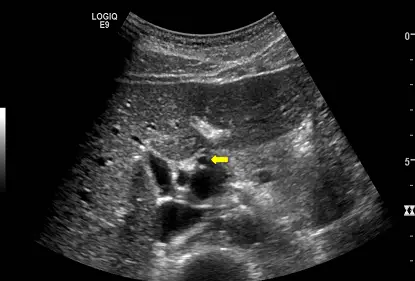

執行肝膽系統超音波掃描,出現如下圖的米老鼠徵象( Micky mouse sign )時,箭號所指的部位為:

在肝膽系統超音波掃描中,「米老鼠徵象」(Mickey mouse sign)是指在肝門部(porta hepatis)進行橫切面(Transverse view)掃描時,門脈三角(portal triad)內三個主要管狀構造所呈現的典型影像特徵。這三個構造分別為門靜脈(Portal vein)、總膽管(Common bile duct)與肝動脈(Hepatic artery)。掌握這三者的相對解剖位置,是醫事放射師在執行腹部超音波時的必備基礎。

- 影像視角:這是一張肝門部的標準超音波橫切面影像。在標準腹部橫切面設定下,畫面的左側代表病患的右側(外側,Lateral),畫面的右側代表病患的左側(內側,Medial)。

- 管腔特徵:影像中央清晰可見三個無回音(anechoic)的管狀構造,共同排列成「米老鼠」的頭部形狀。

- 臉部(下方/後方的大圓):為管徑最大的門靜脈(Portal vein)。

- 右耳(畫面左側/病患外側的小圓):位於門靜脈的前方外側,為總膽管(Common bile duct)。

- 左耳(畫面右側/病患內側的小圓):位於門靜脈的前方內側,為肝動脈(Hepatic artery)。

- 箭頭指示:黃色箭頭明確指向位於畫面右側(米老鼠的左耳)的小型